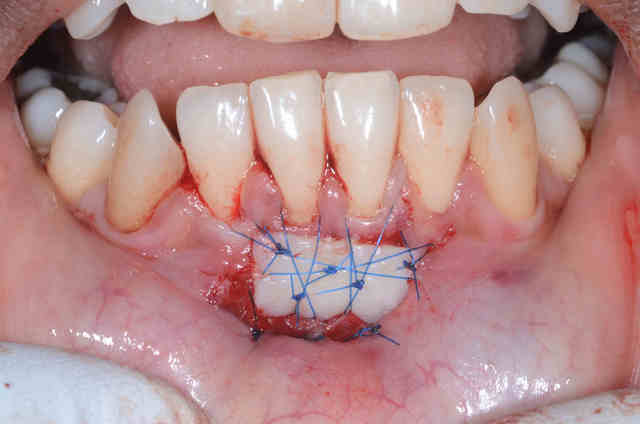

Voila, c`est ma deuxième GGL. Il y avait 0.5mm de gencive attachée sur la 41. On voit la cicatrisation à 48 heures.